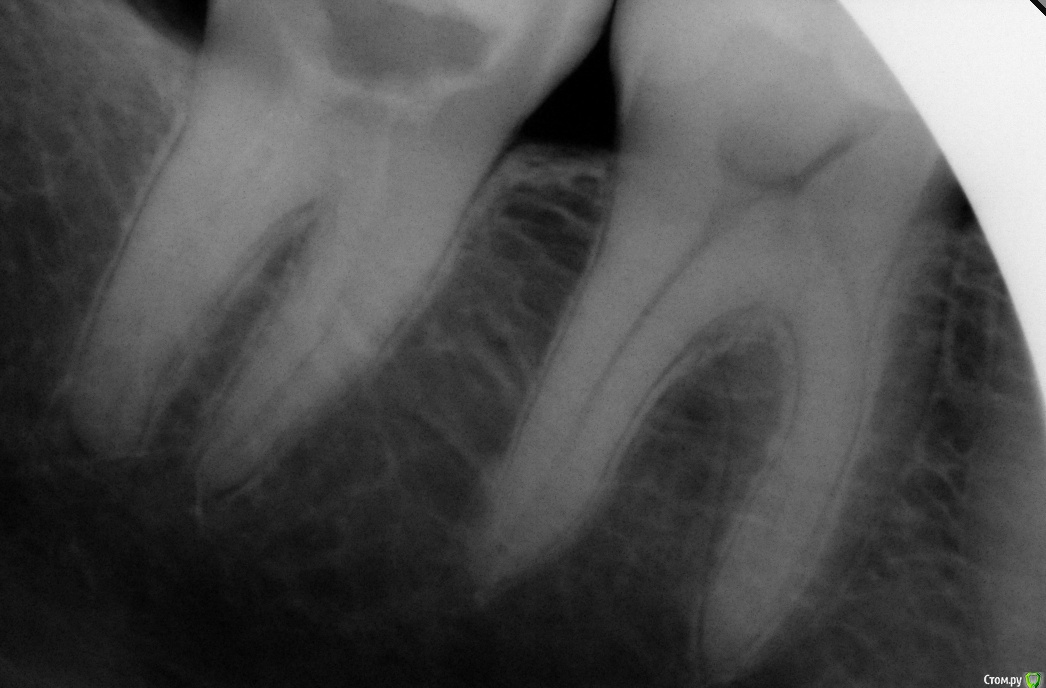

Fatality Опубликовано 7 января, 2018 Автор Поделиться Опубликовано 7 января, 2018 Уважаемые врачи, ищу вашей помощи! У меня нет никаких улучшений со стороны зуба - болит при накусывании, болят стенки при постукивании по ним. Каналы чистили и мыли 4 раза два разных специалиста.13 и 19 декабря после промывки закладывали Каласепт,4 января вскрыли зуб, прочистили и заложили хлоргексидин гель (была нарушена герметичность временной пломбы и врач решил, что в зубе могли начать размножаться грибы Кандида),6 января убрали хлоргексидин и снова положили Каласепт. Мне делали 2 снимка на протяжении лечения, но комментариев по поводу ситуации никто толком не дает. Единственное, сказали, что в коронке зуба появилась трещина, но не знают, дошла ли она до корня. Последний врач сказал, что если воспаление и болевые ощущения не будут проходить, то зуб придется удалить. Я не знаю как нужно поступить в данной ситуации - если нет улучшения в ходе лечения и зуб удалить, либо стоит бороться за зуб и продолжать с периодичностью раз в две недели закладывать лекарство до улучшения ситуации? Пожалуйста, расшифруйте снимки - у меня ощущение, что около корня увеличилось затемнение. Ссылка на комментарий

dok1 Опубликовано 8 января, 2018 Поделиться Опубликовано 8 января, 2018 У вас неполная механическая обработка каналов. Соответственно страдает антисептическая обработка и полнота заполнения временным материалом. Ищите специалиста, который "пройдёт" каналы полностью. Ссылка на комментарий